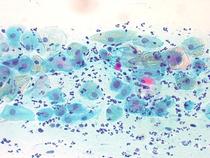

The following images give an idea - 1st is normal cyclic woman, 2nd is post menopausal woman, 3rd is breastfeeding woman and the 4th is a 'borderline' equivocal result that will result in 3 6 month follow ups. It is quite difficult to distinguish between the last 3 and women may end up with false positives and the associated worry until they get a subsequent clear one. Also the endocervix which protrudes in women who are cyclic, becomes internalised in women who are breastfeeding (and postmenopausal) making it more difficult to sample the correct area, risking false negative results.

And an 'borderline' abnormality